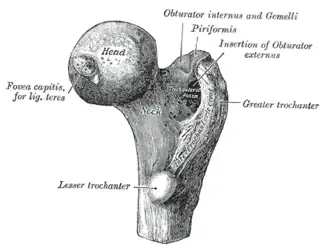

Upper extremity of right femur viewed from behind and above. | |

The head is globular and forms rather more than a hemisphere, is directed upward, medialward, and a little forward, the greater part of its convexity being above and in front.

The femoral head's surface is smooth. It is coated with cartilage in the fresh state, except over an ovoid depression, the fovea capitis, which is situated a little below and behind the center of the femoral head, and gives attachment to the ligament of head of femur.

Fovea capitis

The fovea capitis is a small, concave depression within the head of the femur that serves as an attachment point for the ligamentum teres (Saladin). It is slightly ovoid in shape and is oriented "superior-to-posteroinferior. (Cerezal)" This orientation might be favorable for the tensed fibers of the ligamentum teres. The fovea capitis is located "slightly posterior and inferior to the center of the articular surface of the femoral head (Cerezal)" Unlike the head of the femur, the fovea capitis lacks any hyaline cartilage. The fovea capitis may contain vascular canals in two-thirds of individuals, but "their contribution to femoral head vascularity varies. (Cerezal)"